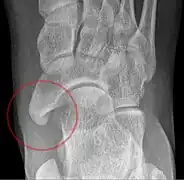

X-ray of the foot showing an accessory navicular bone

An accessory navicular bone is an accessory bone of the foot that occasionally develops abnormally in front of the ankle towards the inside of the foot. This bone may be present in approximately 2-21% of the general population and is usually asymptomatic.[1][2][3] When it is symptomatic, surgery may be necessary.